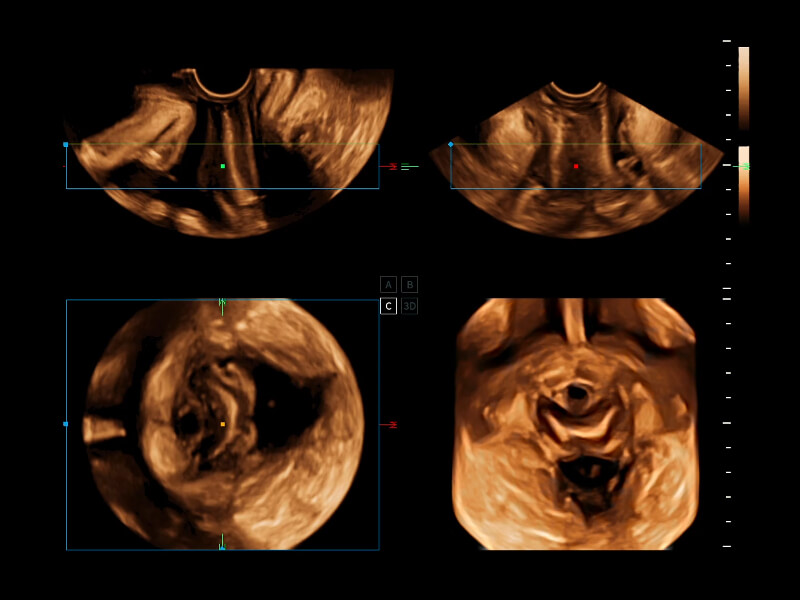

梦溪®P80以“关爱女性”为基石,提供全方位的解决方案,量身定制以满足女性的健康需求,涵盖妇科、生殖健康检查、产前筛查及产后康复等领域。

通过工作流协议、远程访问、自动探头激活和人体工程学优化设计等功能,旨在提高临床工作效率